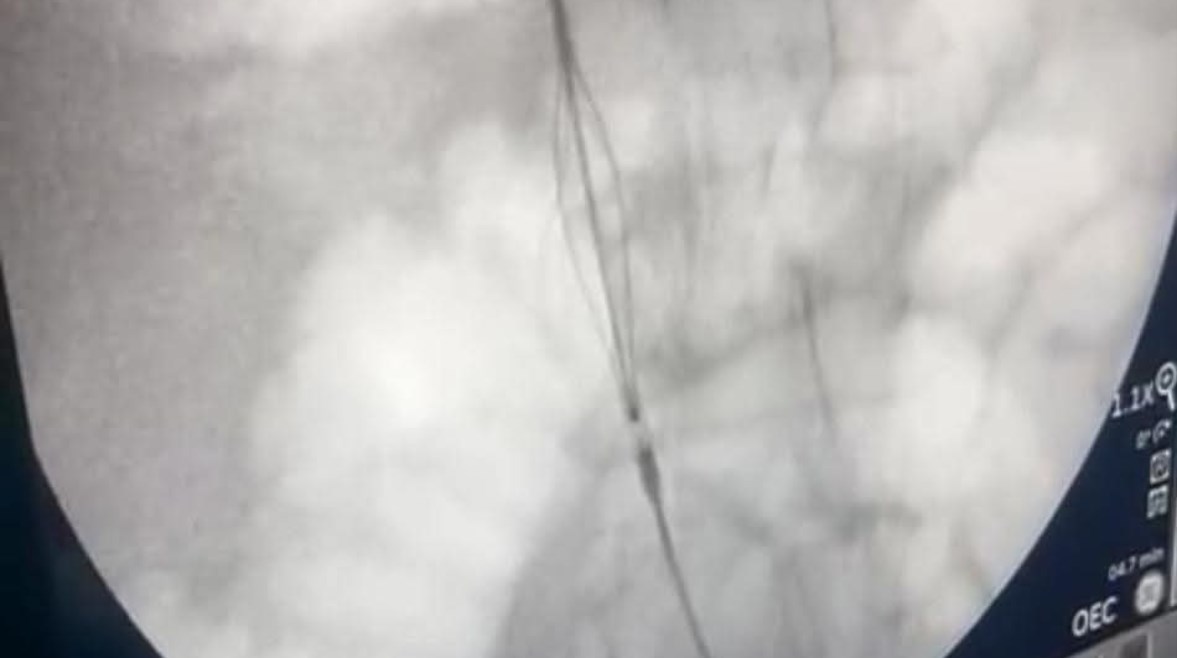

جانب من العملية

نجح فريق طبي بقسم جراحة الأوعية الدموية بمستشفيات جامعة قنا، في استحداث خدمة طبية دقيقة ومتقدمة من خلال إجراء تركيب فلتر وريدي بالوريد الأجوف السفلي (IVC Filter) باستخدام القسطرة التداخلية، وذلك للوقاية من حدوث الجلطات الدموية ومنع انتقالها إلى الشريان الرئوي (Pulmonary Embolism)، بما يسهم في إنقاذ حياة المرضى المعرضين لمضاعفات خطيرة.

وأضاف أيضا أنه تم التعامل مع الحالة وفق أحدث البروتوكولات الطبية، حيث تم استخدام جهاز الأشعة التلفزيونية لعمل مدخل وريدي بالطرف السفلي الأيسر، ثم إجراء تصوير بالصبغة (Cavogram) لتحديد موضع الوريد الكلوي الأيمن (Right Renal Vein)، ومن ثم تركيب الفلتر الوريدي بدقة تحت توجيه القسطرة التداخلية.